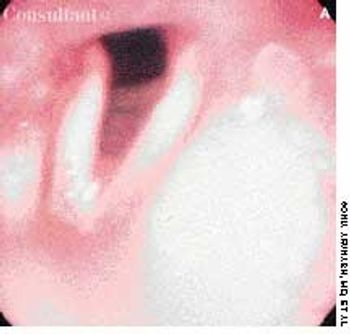

A 72-year-old morbidly obese man who had diabetes mellitus was admitted to the hospital from a nursing home with a fever of 4 days' duration. A tracheostomy had been performed 3 months earlier for respiratory failure. The patient was being treated with corticosteroids for chronic obstructive pulmonary disease.